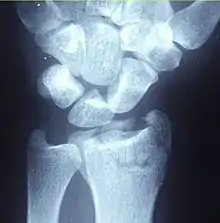

| Fracture of the radial styloid process with the fracture line extending into the intraarticular surface | |

| X-ray of a displaced intra-articular distal radius fracture in an external fixator. The articular surface is widely displaced and irregular. This is a Chauffeur's fracture. Frykman class 3. | |